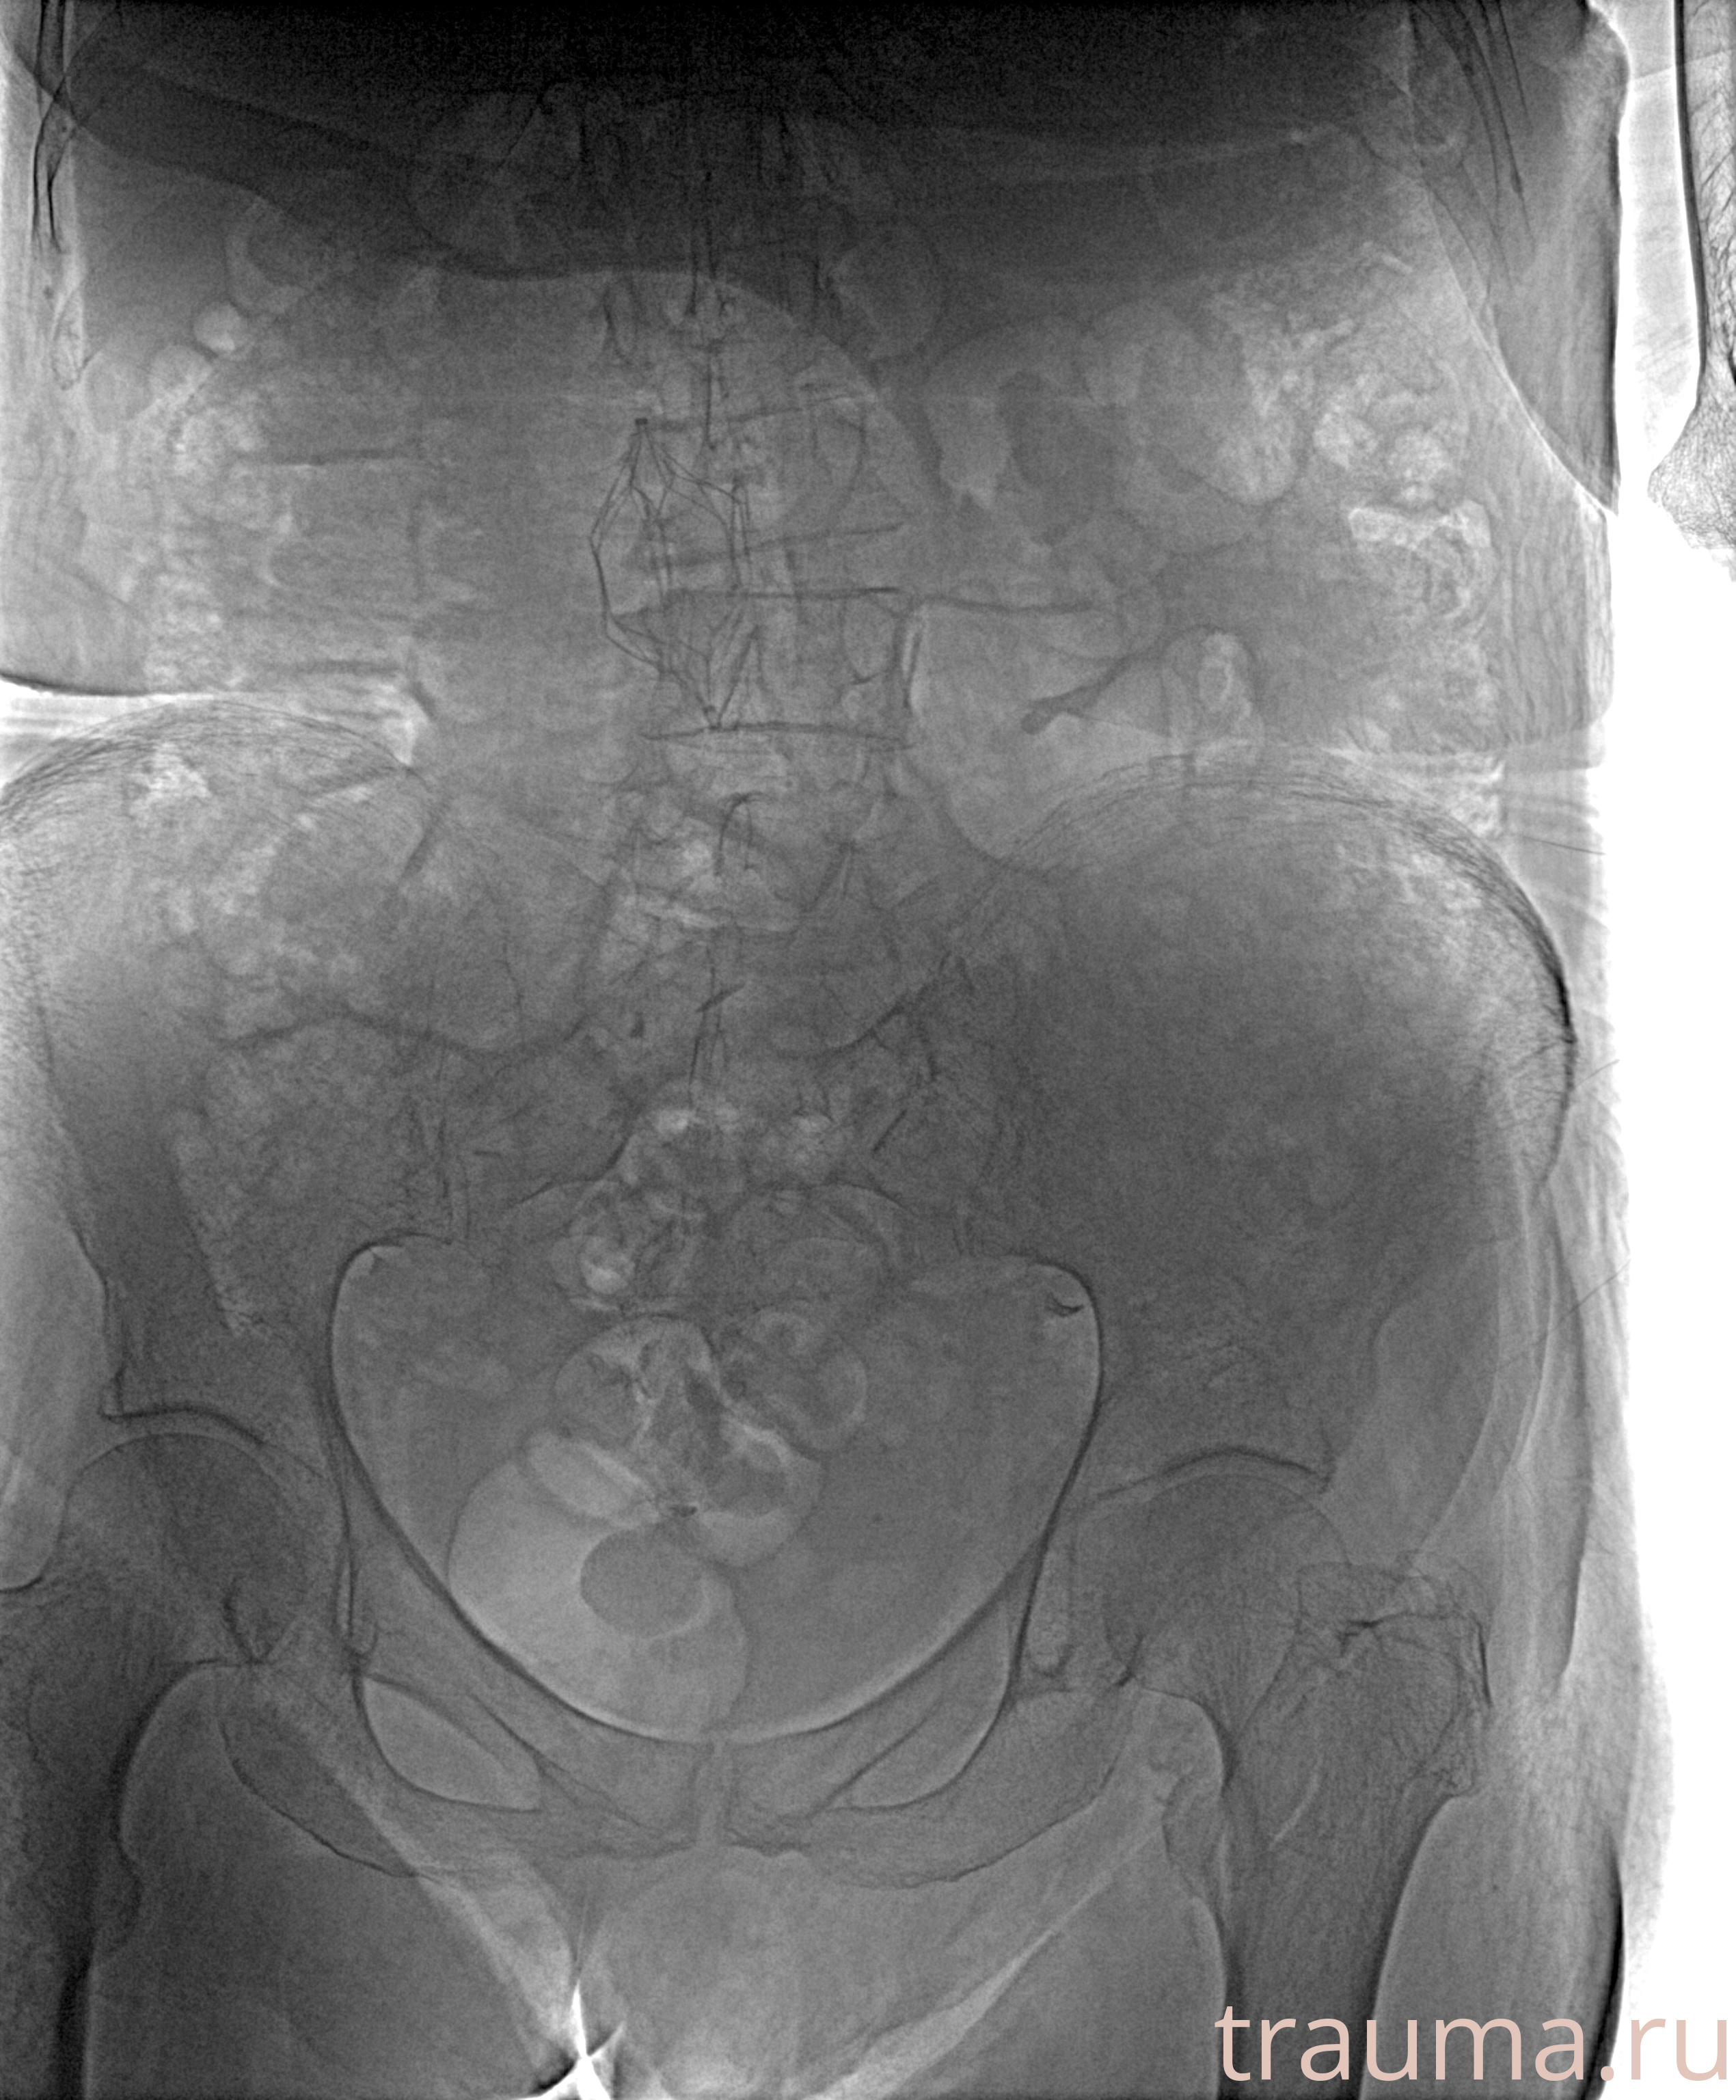

Рентгенограммы

Рентген на дому: по вашему адресу приезжает врач-рентгенолог, травматолог-ортопед с мобильным рентгеновским аппаратом, проводит диагностику травмы или заболевания, делает необходимые рентгенограммы, дает рекомендации по дальнейшему лечению. Получить качественные снимки в домашних условиях возможно благодаря уникальной методике, разработанной МосРентген Центром для института  Склифосовского

при переломе шейки бедра и пневмонии от компании МосРентген Центр - партнера Института имени Склифосовского